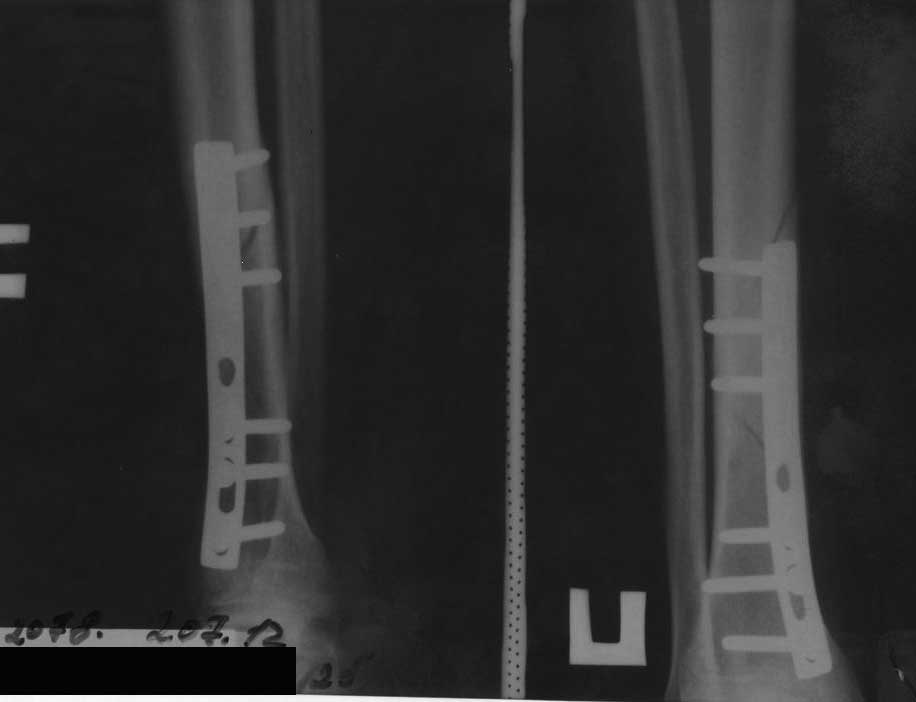

Повторный перелом н/3 большеберцовой кости с наличием металлофиксаторов |

Травма бытовая 28.01.2012. Госпитализирован в травм. отделение. 30.01.2012 выполнено оперативное вмешательство - открытая репозиция, металлоостеосинтез накостной пластиной (сразу приношу извинения за качество п/о рентгенограмм, к тому же, у больного сохранился снимок только в прямой проекции). П/о период без особенностей. Выписан на амбулаторное лечение. Через 4 месяца - полная нагрузка на ногу, вёл обычный образ жизни. 02.07.2012 спрыгнул с дерева и внезапно почувствовал сильную боль в голени. На рентгенограмме - повторный перелом.

Временно наложен сапожок HM Cast. Вопрос: что делать? Оставить так как есть? Открыться и поставить пластину подлиннее(на б/б стержень у больного нет $)? По-моему, линия излома проходит через места выхода винтов, боюсь, как бы они не стали "распоркой" для костных отломков и не стали препятствовать сращению...